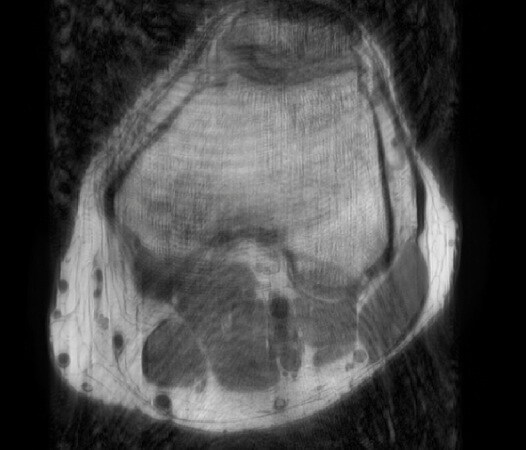

Radiologist sitting behind the MRI console looking at clinical images acquired with Compressed SENSE

Magnetic Resonance

Compressed SENSE

Up to 50% faster MRI scans with virtually equal image quality1

Philips Compressed SENSE is a cutting-edge MRI technology that significantly speeds up scans while delivering virtually equal image quality. By intelligently compressing data, it accelerates your existing MR scans by up to 50%, frees up time to improve your patient experience and can provide up to 60% higher resolution to enhance diagnostic confidence.1 Philips Compressed SENSE is suitable for all anatomies and can be used for all anatomical contrasts, in both 2D and 3D.